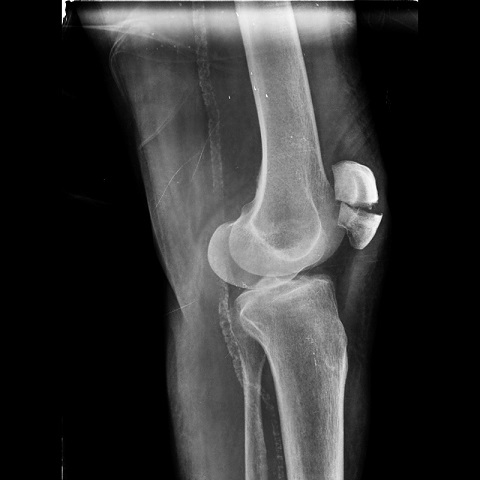

3- تشخیص شکستگی کشکک:

رادیوگرافی مهمترین وسیله برای تشخیص این شکستگی است. بندرت در بعضی افراد ممکن است استخوان کشکک دو تکه ای باشد که نباید با شکستگی اشتباه شود. در اکثر این افراد اگر از زانوی مقابل هم رادیوگرافی به عمل آید این کشکک دو تکه ای دیده میشود .

ممکن است با استفاده از روش های غیر جراحی و یا جراحی انجام شود .در صورتیکه قطعات شکسته شده بدون جابجایی باشند درمان غیر جراحی است. به این صورت که پزشک معالج ابتدا خون داخل زانو را با سرنگ خارج کرده و سپس با استفاده از گچ بلند اندام تحتانی، زانو را یک و نیم ماه در حالت راست و مستقیم نگه داشته تا استخوان های شکسته شده جوش بخورند. اما اگر قطعات شکسته شده از هم جدا شده باشند بیمار نیاز به عمل جراحی دارد به این معنی که پزشک در اطاق عمل پوست را برش میدهد و در زیر آن استخوان شکسته شده کشکک نمایان میشود. جراح سپس قطعات شکسته شده را با ابزارهای بخصوصی در کنار یکدیگر قرار داده و سپس به توسط پین و سیم های فولادی آنها را در کنار یکدیگر محکم میکند.